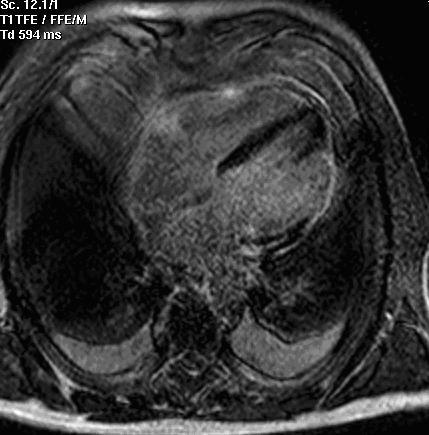

Delayed-enhancement magnetic resonance imaging (DE-MRI) has been recently proposed as an alternative tool in identifying myocardial viability and transmural distribution of necrosis in the myocardium.

We describe a case of a 71-year-old man admitted for ischemic-like chest pain in which DE-MRI and post-nitrate 99mTc-tetrofosmin myocardial scintigraphy equally contributed to the diagnosis of previous lateral myocardial infarction.

In this patient with coronary artery disease, the absence of uptake of tracer at myocardial scintigraphy appeared to be closely correlated to DE-MRI data. Cardiologists can use SPECT or DE-MRI to obtain similar information about myocardial viability.